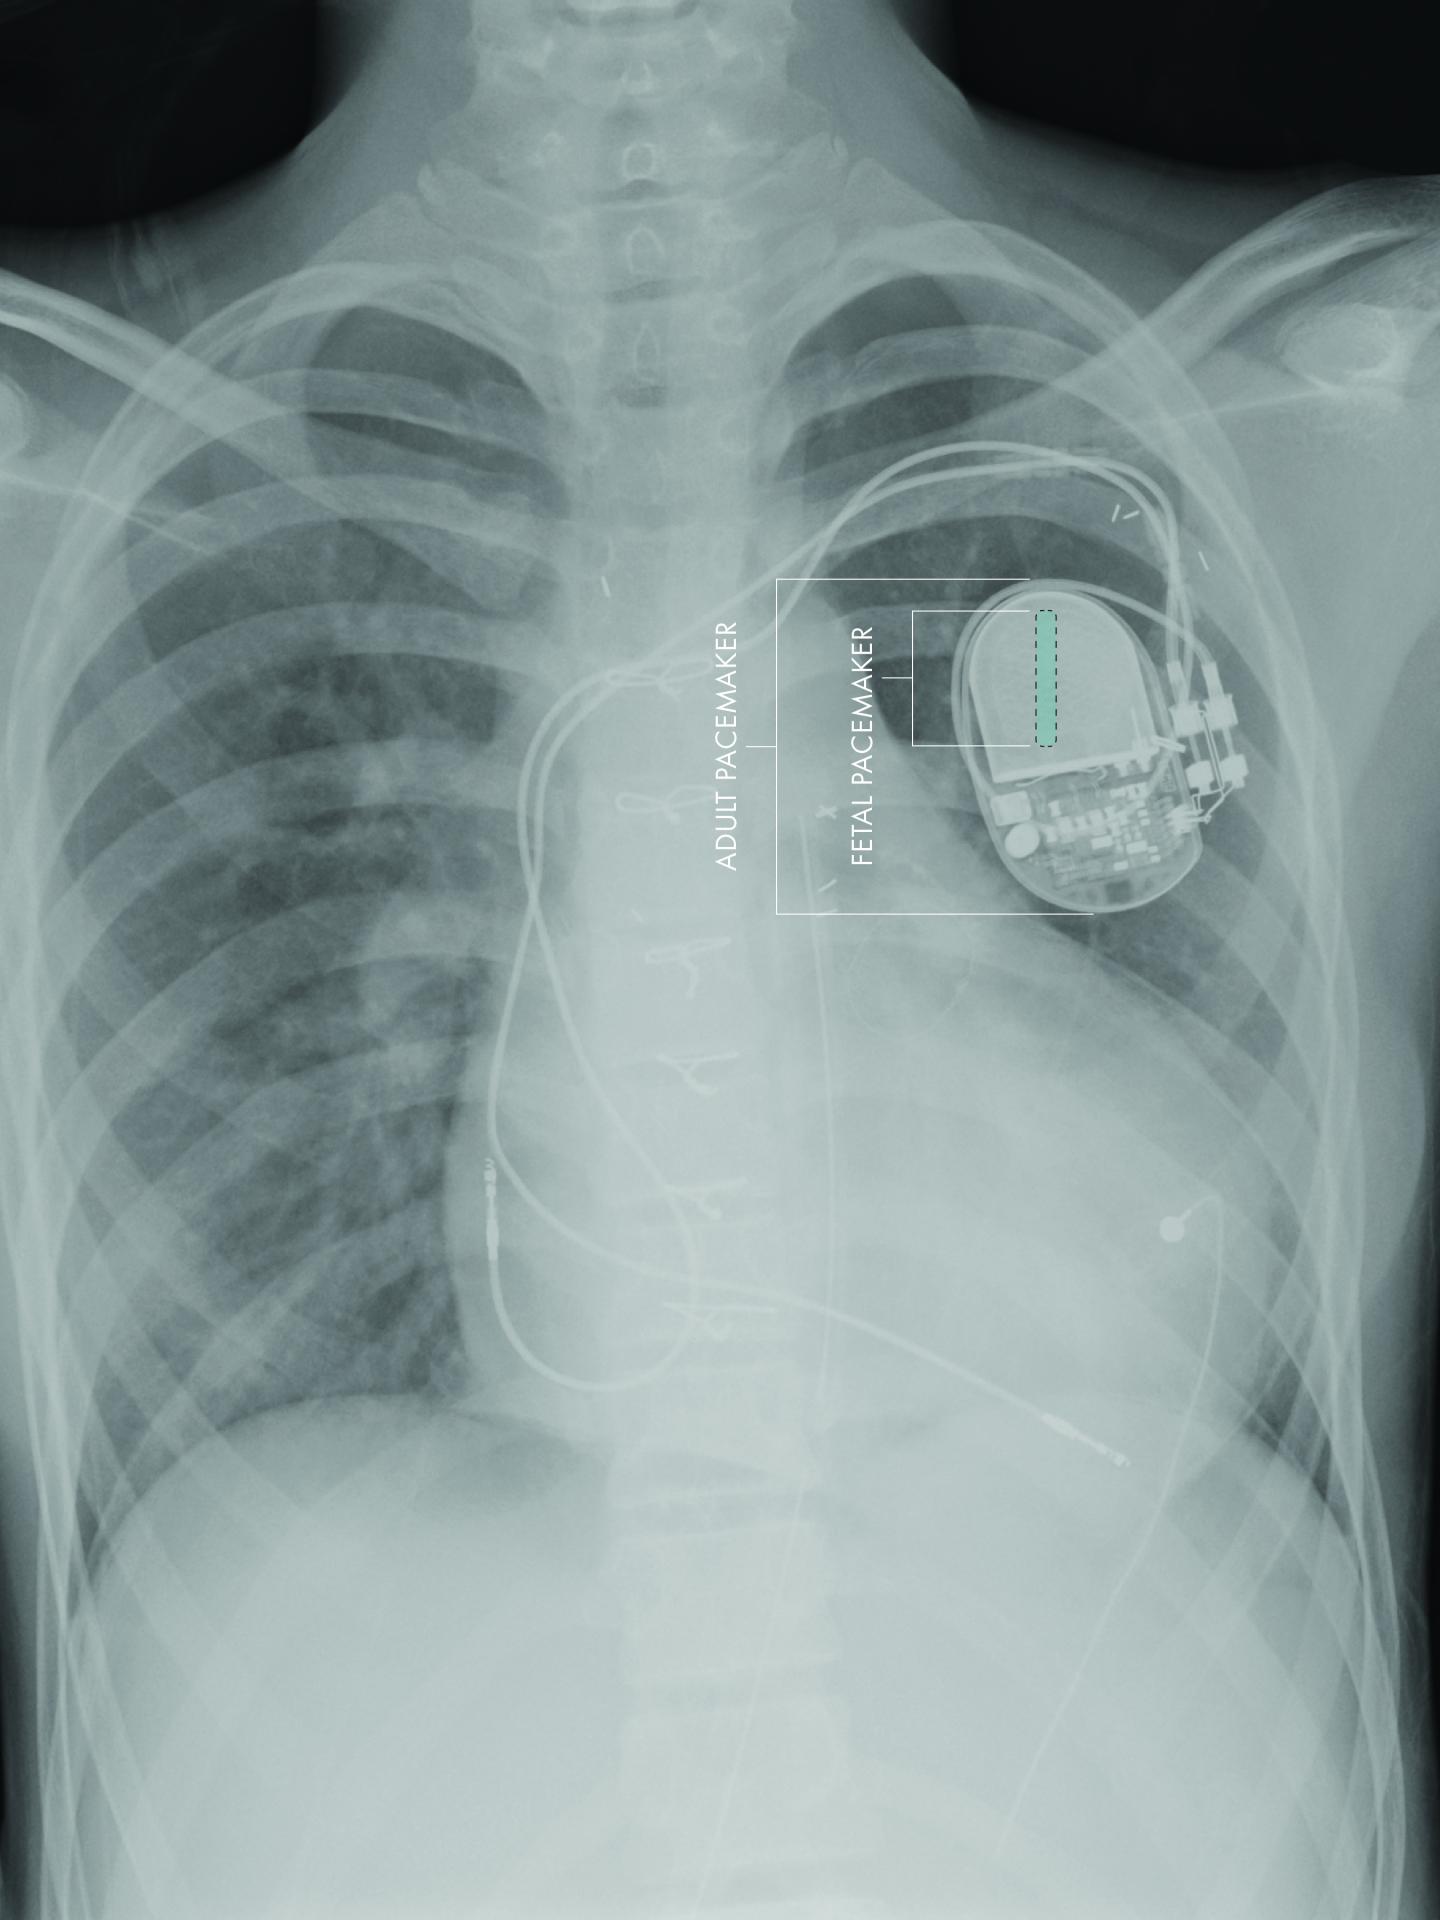

A team of investigators at Children's Hospital Los Angeles and the University of Southern California have developed the first fully implantable micropacemaker designed for use in a fetus with complete heart block. The team has done preclinical testing and optimization as reported in a recent issue of the journal Heart Rhythm . The micropacemaker has been designated a Humanitarian Use Device by the US Food & Drug Administration (FDA). The investigators anticipate the first human use of the device in the near future.

The size of the adult device requires a small part to be implanted in the fetus and the rest to remain externalized. This design has uniformly failed, likely due to fetal movement causing the electrodes to become dislodged from the heart.

"Building on our experience of using microfabrication techniques to create biomedical devices, we have developed a micropacemaker small enough to reside entirely within the fetus," said Gerald E. Loeb, MD, professor of Biomedical Engineering at the Viterbi School of Engineering at USC. "This will allow the fetus to move freely without risk of dislodging the electrodes."